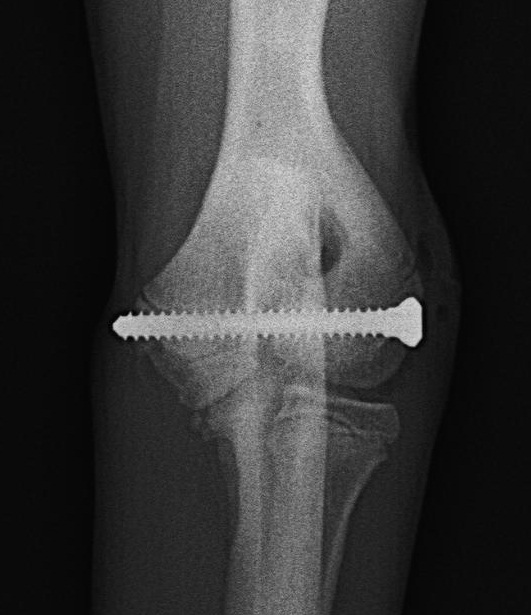

Como casi siempre (el casi lo contaré en otra entrada) decidimos la resolucion mediante el abordaje lateral, y colocacion de un tornillo intercondilar con aguja antirrotacional

Et voilá!. Encontramos la linea radiolucida entre los dos procesos del condilo que son indicativas de la existencia de una OICH (osificacion incompleta del condilo humeral).

De esta manera, en el mismo acto quirurgico, y practicamente a cielo cerrado, podemos colocar un tornillo de compresion intercondilar en la pata sana que dé resistencia y favorezca la completa osificacion.